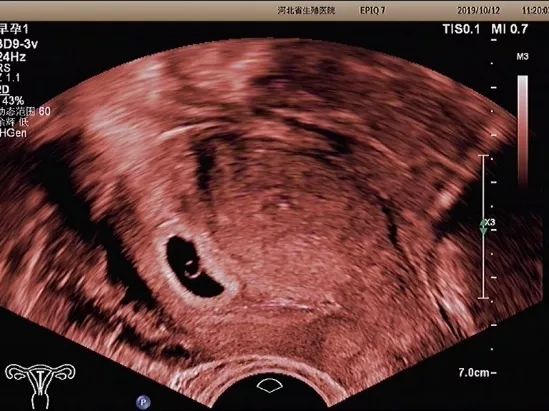

孕早期超声检查的内容

孕早期超声检查的内容主要有

以下5个方面

妊娠囊

确定妊娠囊是否在宫腔内,妊娠囊在宫腔内的位置、数目及大小。妊娠囊的大小可随孕周增长而增长。

卵黄囊

卵黄囊是妊娠囊内超声能发现的第一个解剖结构。当超声发现卵黄囊,即可以确定妊娠。正常的卵黄囊直径约3~8mm,卵黄囊过大、过小或不显示及变形均提示妊娠结局不良。

胚芽

可根据胚芽长度评估孕周,有无心管搏动,确定胚胎是否存活。

经阴道超声检查

经阴道超声检

查又称腔内超声

孕妇取膀胱截石位

在腔内超声探头上

套上无菌避孕套

将探头伸入阴道进行检查